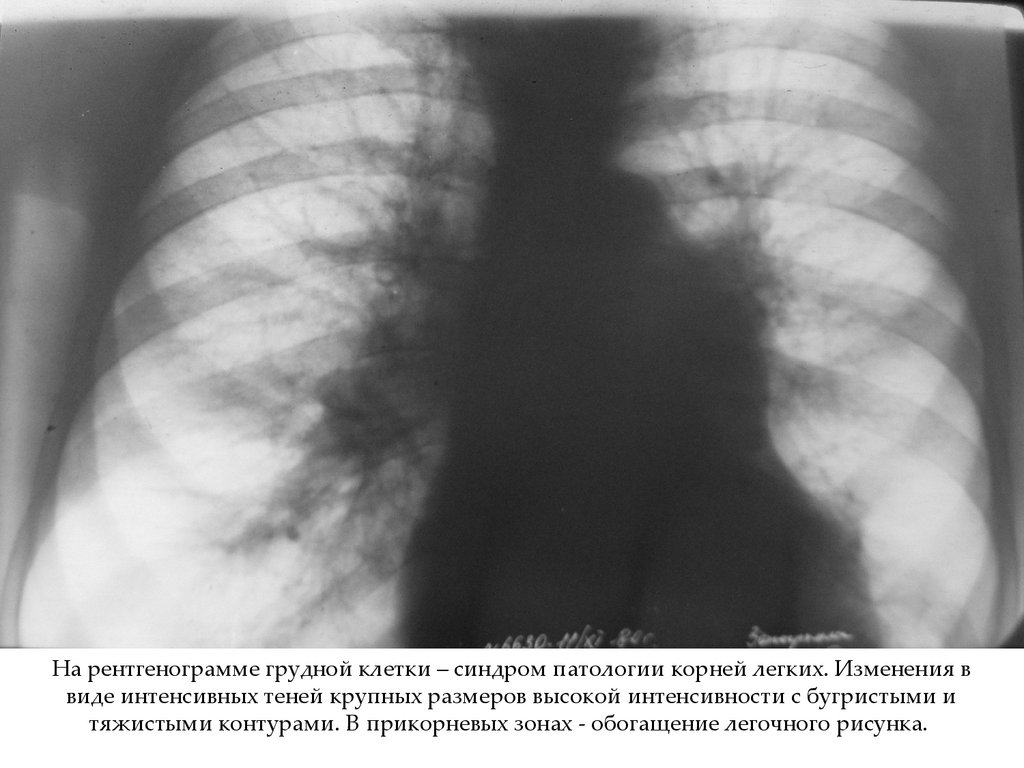

На рентгенограмме грудной клетки – синдром патологии корней легких. Изменения в

виде интенсивных теней крупных размеров высокой интенсивности с бугристыми и

тяжистыми контурами. В прикорневых зонах - обогащение легочного рисунка.